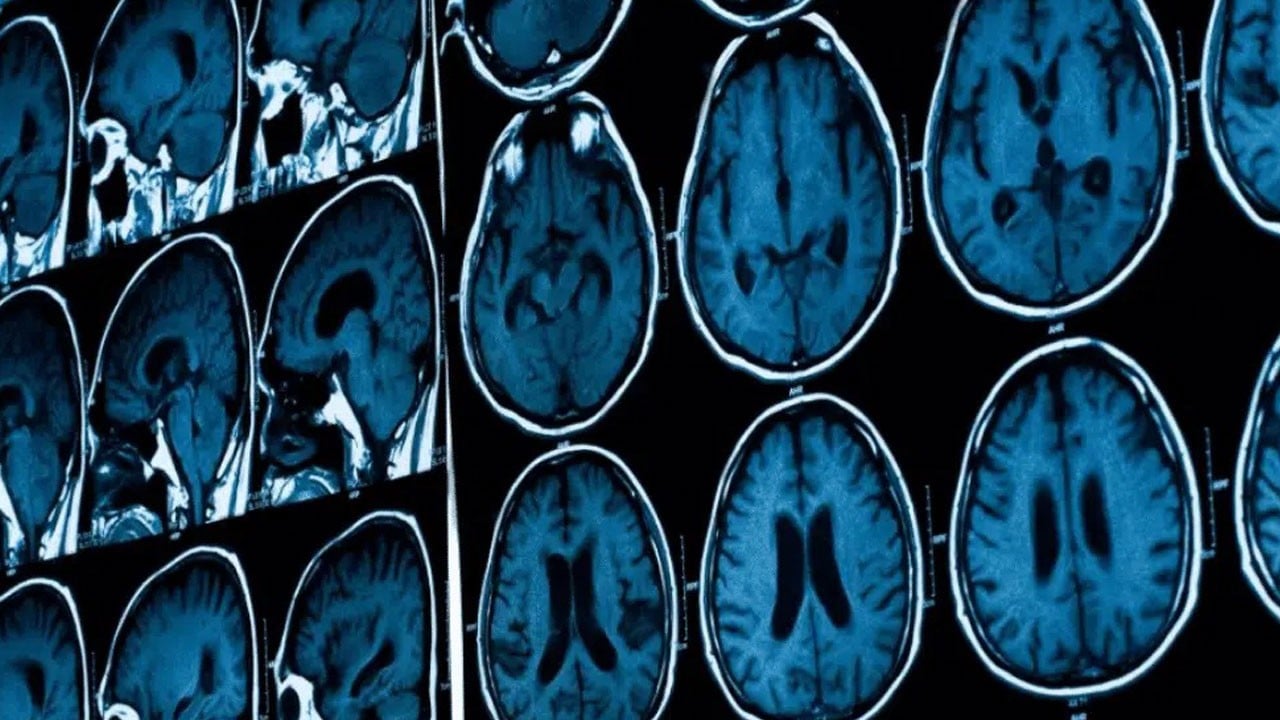

Migrenin uzun vadede beyin hasarı oluşturduğu doğru mu?

Uzman incelemeleri, bazı migren hastalarının beyin görüntülerinde beyaz madde lezyonları görülebildiğini ortaya koyuyor. Ancak araştırmalar bu lezyonların beyin fonksiyonunu bozmadığını, bilişsel becerilerde düşüşe yol açmadığını ve kalıcı hasar oluşturmadığını gösteriyor.